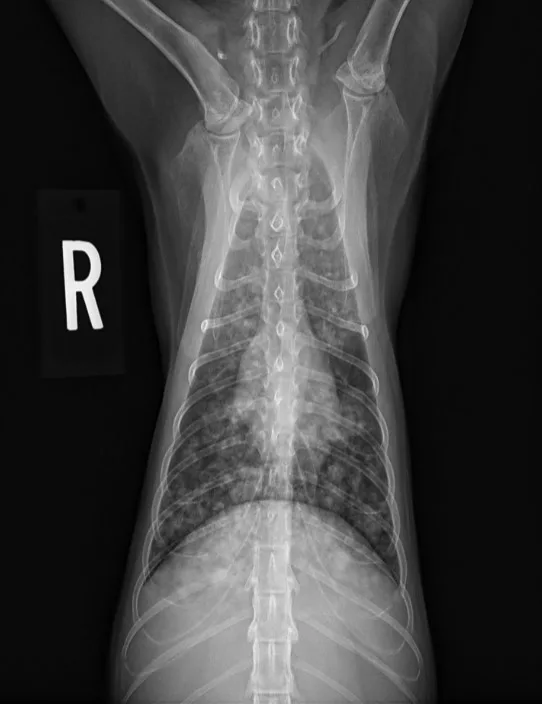

At the 2-month recheck, continued clinical improvement was observed. The owner reported Eleanor was doing well at home. Her body weight had increased to 8.3 lb (3.8 kg); BCS was 4/9.On physical examination, mildly increased bronchovesicular sounds were still present. Fundic examination results were normal. Thoracic radiographs showed continued improvement; remaining lesions were predominantly in the peripheral lung field with a more caudodorsal distribution (Figure 3).

A

FIGURE 3 Left lateral (A), right lateral (B), and ventrodorsal (C) thoracic radiographs 2 months after initiation of itraconazole. Remaining lesions (arrows) were predominantly in the peripheral lung field with a more caudodorsal distribution.